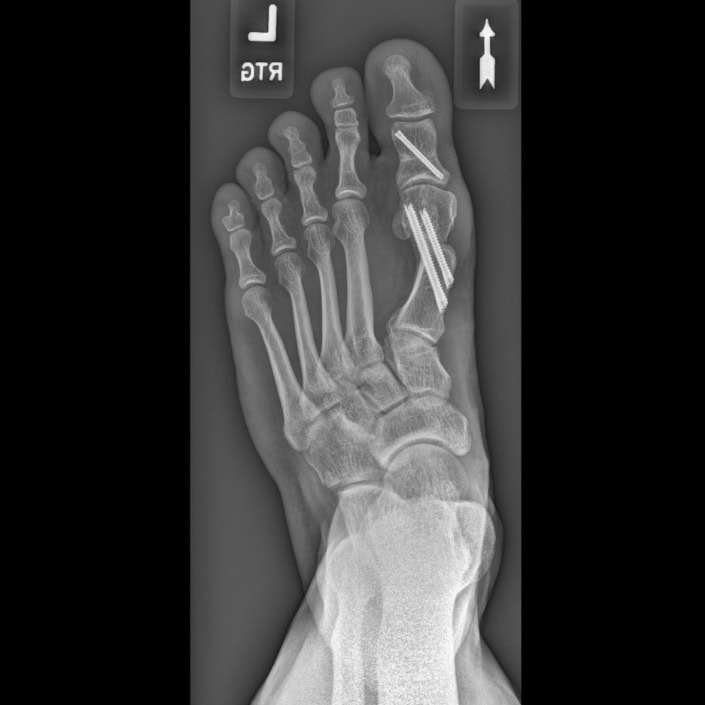

W przypadku braku skuteczności leczenia zachowawczego lub znacznego nasilenia deformacji, których efektem jest znaczące ograniczenie komfortu życia, wskazane jest leczenie operacyjne. Dobór techniki operacyjnej jest uzależniony od stopnia deformacji, wieku i oczekiwań funkcjonalnych pacjenta.

Najczęściej obejmuje ono:

- osteotomie korekcyjne I kości śródstopia z wykorzystaniem takich technik operacyjnych jak Chevron, Scarf, Ludloff, czy osteotomie przypodstawne – często w połączeniu z osteotomią paliczka bliższego palucha (Akin),

- uwolnienia tkanek miękkich – więzadeł stabilizujących trzeszczkę boczną, czasem przywodziciela palucha i/lub inne,

- artrodezę Lapidusa, czyli usztywnienie stawu klinowo-śródstopnego pierwszego w odpowiedniej pozycji,

- artrodezę, czyli usztywnienie stawu śródstopno-palcowego pierwszego – stosowane głównie u pacjentów z chorobami reumatoidalnymi lub neurologicznymi oraz w przypadkach zaawansowanej deformacji.